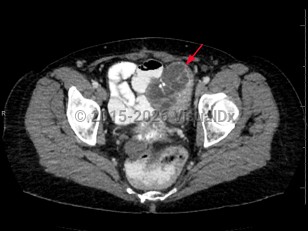

Ovarian cancerOvarian cancer

Endometrial carcinomaEndometrial carcinoma

Uterine cancer

Cervical cancer